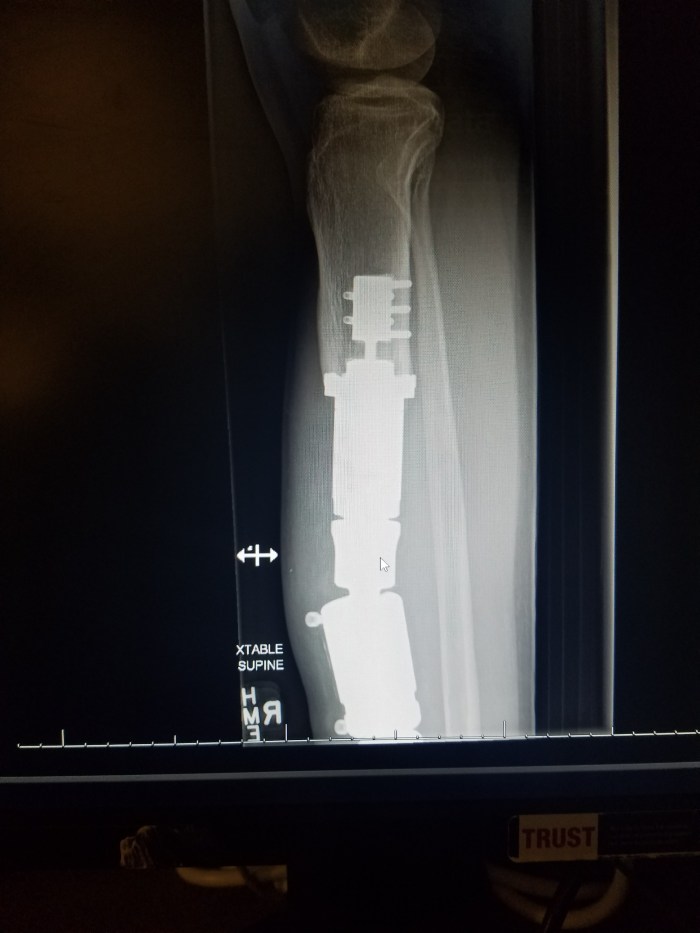

Remember that cool implant in Greg’s leg? Today he heard a “pop” and then this happened. It is past midnight and we still don’t have answers… so stay tuned for the rest of the story.